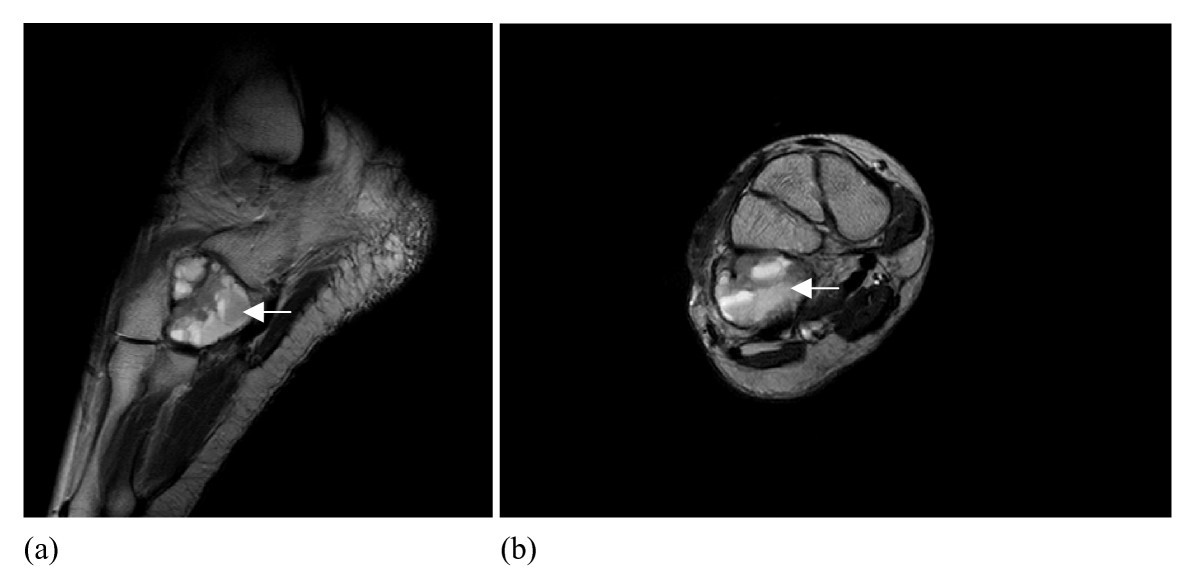

🧲 Resonancia magnética (RM)

La RM define con precisión la extensión intraósea y la relación con el cartílago articular y las partes blandas. Es característico el edema óseo perilesional marcado, que puede simular una lesión más agresiva de lo que realmente es. La RM es esencial para planificar la biopsia (seleccionando la zona más representativa) y el curetaje.

RM de condroblastoma con quiste óseo aneurismático asociado. Imagen basada en Sepah YJ, Umer M, Minhas K, et al. Journal of Medical Case Reports (2007), figura 2. Licencia CC BY 2.0.

Trampa frecuente: una RM con edema óseo y realce intenso no equivale a malignidad. La correlación con la radiografía simple, la TC y la histología es fundamental para evitar sobretratamiento.